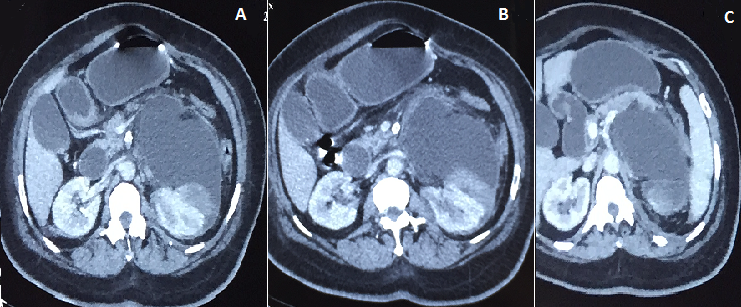

Madame RF âgée de 50 ans, diabétique sous insuline mal suivie compliquée d'une neuropathie optique au stade de pré-cécité, avec une artériopathie oblitérante du membre inferieure . La patiente consultait pour les lombalgies. A l'examen clinique on retrouve une patiente apyrétique, présentant un contact lombaire. La bandelette urinaire était négative. Le bilan biologique était correct, la sérologie hydatique était négative. Sur le plan radiologique, l'échographie abdominale mettait en évidence une énorme masse liquidienne rétro-péritonéale gauche refoulant le rein gauche vers l'arrière. L'Uro-scanner retrouvait une masse kystique de 18 cm, rétro péritonéale et occupant la quasi-totalité de cet espace. Sur les coupes coronales, elle refoulait vers l'avant le péritoine. Par ailleurs, l'absence de dilatation des voies excrétrices nous permet d'évoquer les hypothèses suivantes: une rupture de fornix, une duplicité rénale ou un lymphangiome kystique. Enfin l'Uretero-pyelographie rétrograde a permis de trancher pour un urinome, car elle a mis en exergue l'extravasation du PC. En ce qui concerne la pris en charge, une sonde JJ a été laissée en place jusqu'à assèchement de la collection.